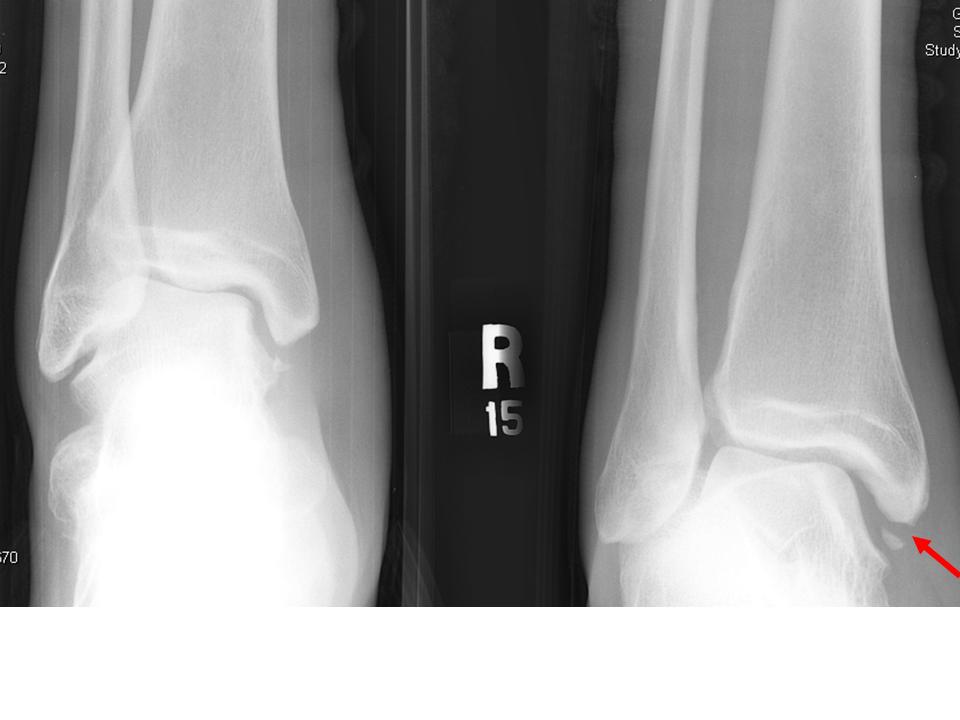

Another patient with a Maisonneuve fracture.